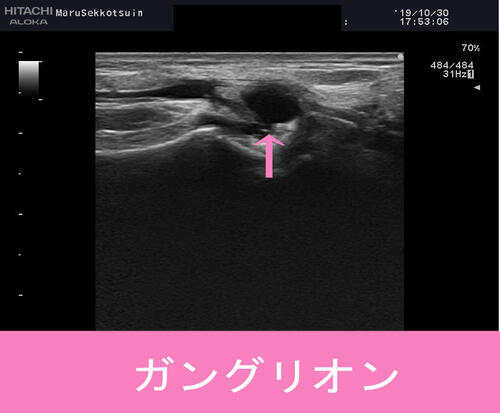

しっかり触診、視診、そして確認の為、エコー検査。

結果、腫瘤の流動性もあることから「ガングリオン」の疑い。

ガングリオンとは中にゼリー状の物質が詰まった腫瘤で、

関節の周囲によく発生し、女性に多くできるコブです。

基本的には無痛の場合が多いですが、神経の近くや、

血管を圧迫している場合などは、痛みや麻痺が出現する場合もあるので注意が必要です。